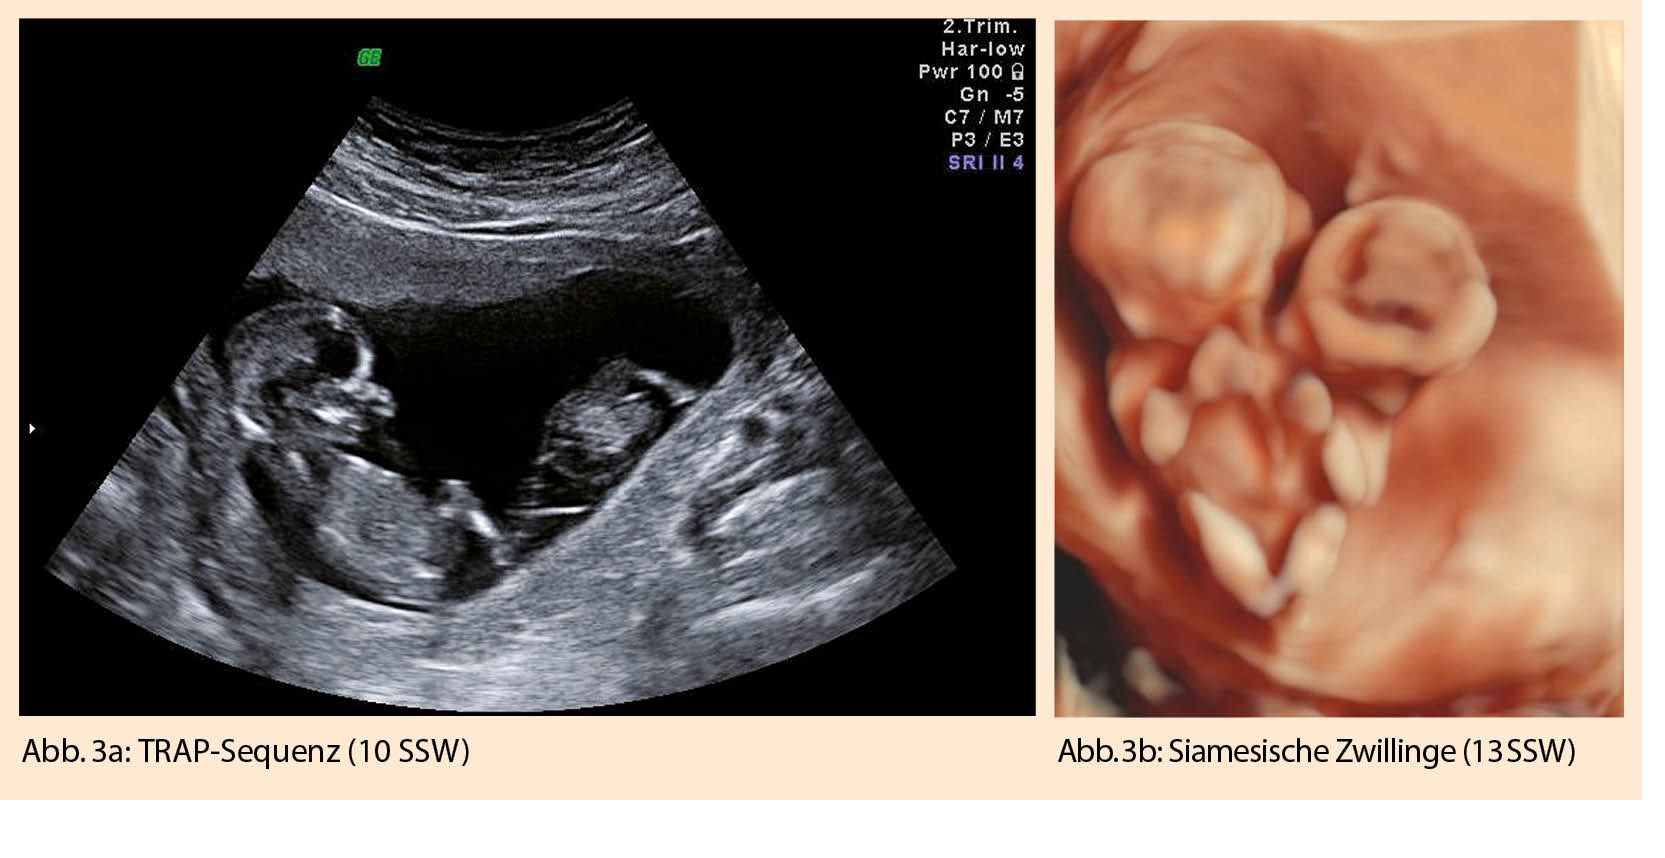

Sieht man sonographisch zwei klar getrennte, von Throphoblast umgebene Fruchthöhlen, liegt eine dichoriale diamniote Schwangerschaft vor. Um 12-14 SSW entwickelt sich daraus das typische «Lambda»-Zeichen (Abb. 2a), da nur noch plazentaseitig ein Choriondreieck zwischen die beiden Amnionblätter zieht. In 7% verschwindet das Lambda-Zeichen nach 20 SSW (10).

Findet sich nur eine Fruchthöhle mit zwei Embryonen, liegt eine monochoriale Zwillingsschwangerschaft vor. Bei monochorialen diamnioten Zwillingen liegen die beiden Amnionblätter glatt aufeinander und bilden so eine feine Trennwand zwischen den Feten. Bei 8-10 SSW sind die beiden Amnionblätter meist noch etwas vom Chorionblatt abgelöst, wodurch sonographisch der Eindruck eines leeren «Lambda»-Zeichens oder auch das typische Bild eines «Mercedesstern»-Zeichens erscheint (Abb. 2b). Sobald die Amnion- und Chorionblätter vollständig verschmelzen bildet sich das «T»-Zeichen.

Vor 8-10 SSW ist die Amniozität oft noch schwierig zu beurteilen. Die Dottersackdiagnostik hilft hierbei auch nicht weiter. Bei einer Monoamnionizität, ca. 4% aller monochorialen Schwangerschaften, lässt sich auch bei 10-14 SSW keine Trennwand zwischen den Embryonen darstellen. Typischerweise zeigt sich eine Amnionhöhle mit zwei eng zusammenliegenden Nabelschnuransätzen oder einer Nabelschnurverdrillung (Abb.  2c). Die Messung der Membrandicke und das Zählen der Membranschichten zwischen den Feten sind keine zuverlässigen Diagnosekriterien (10).